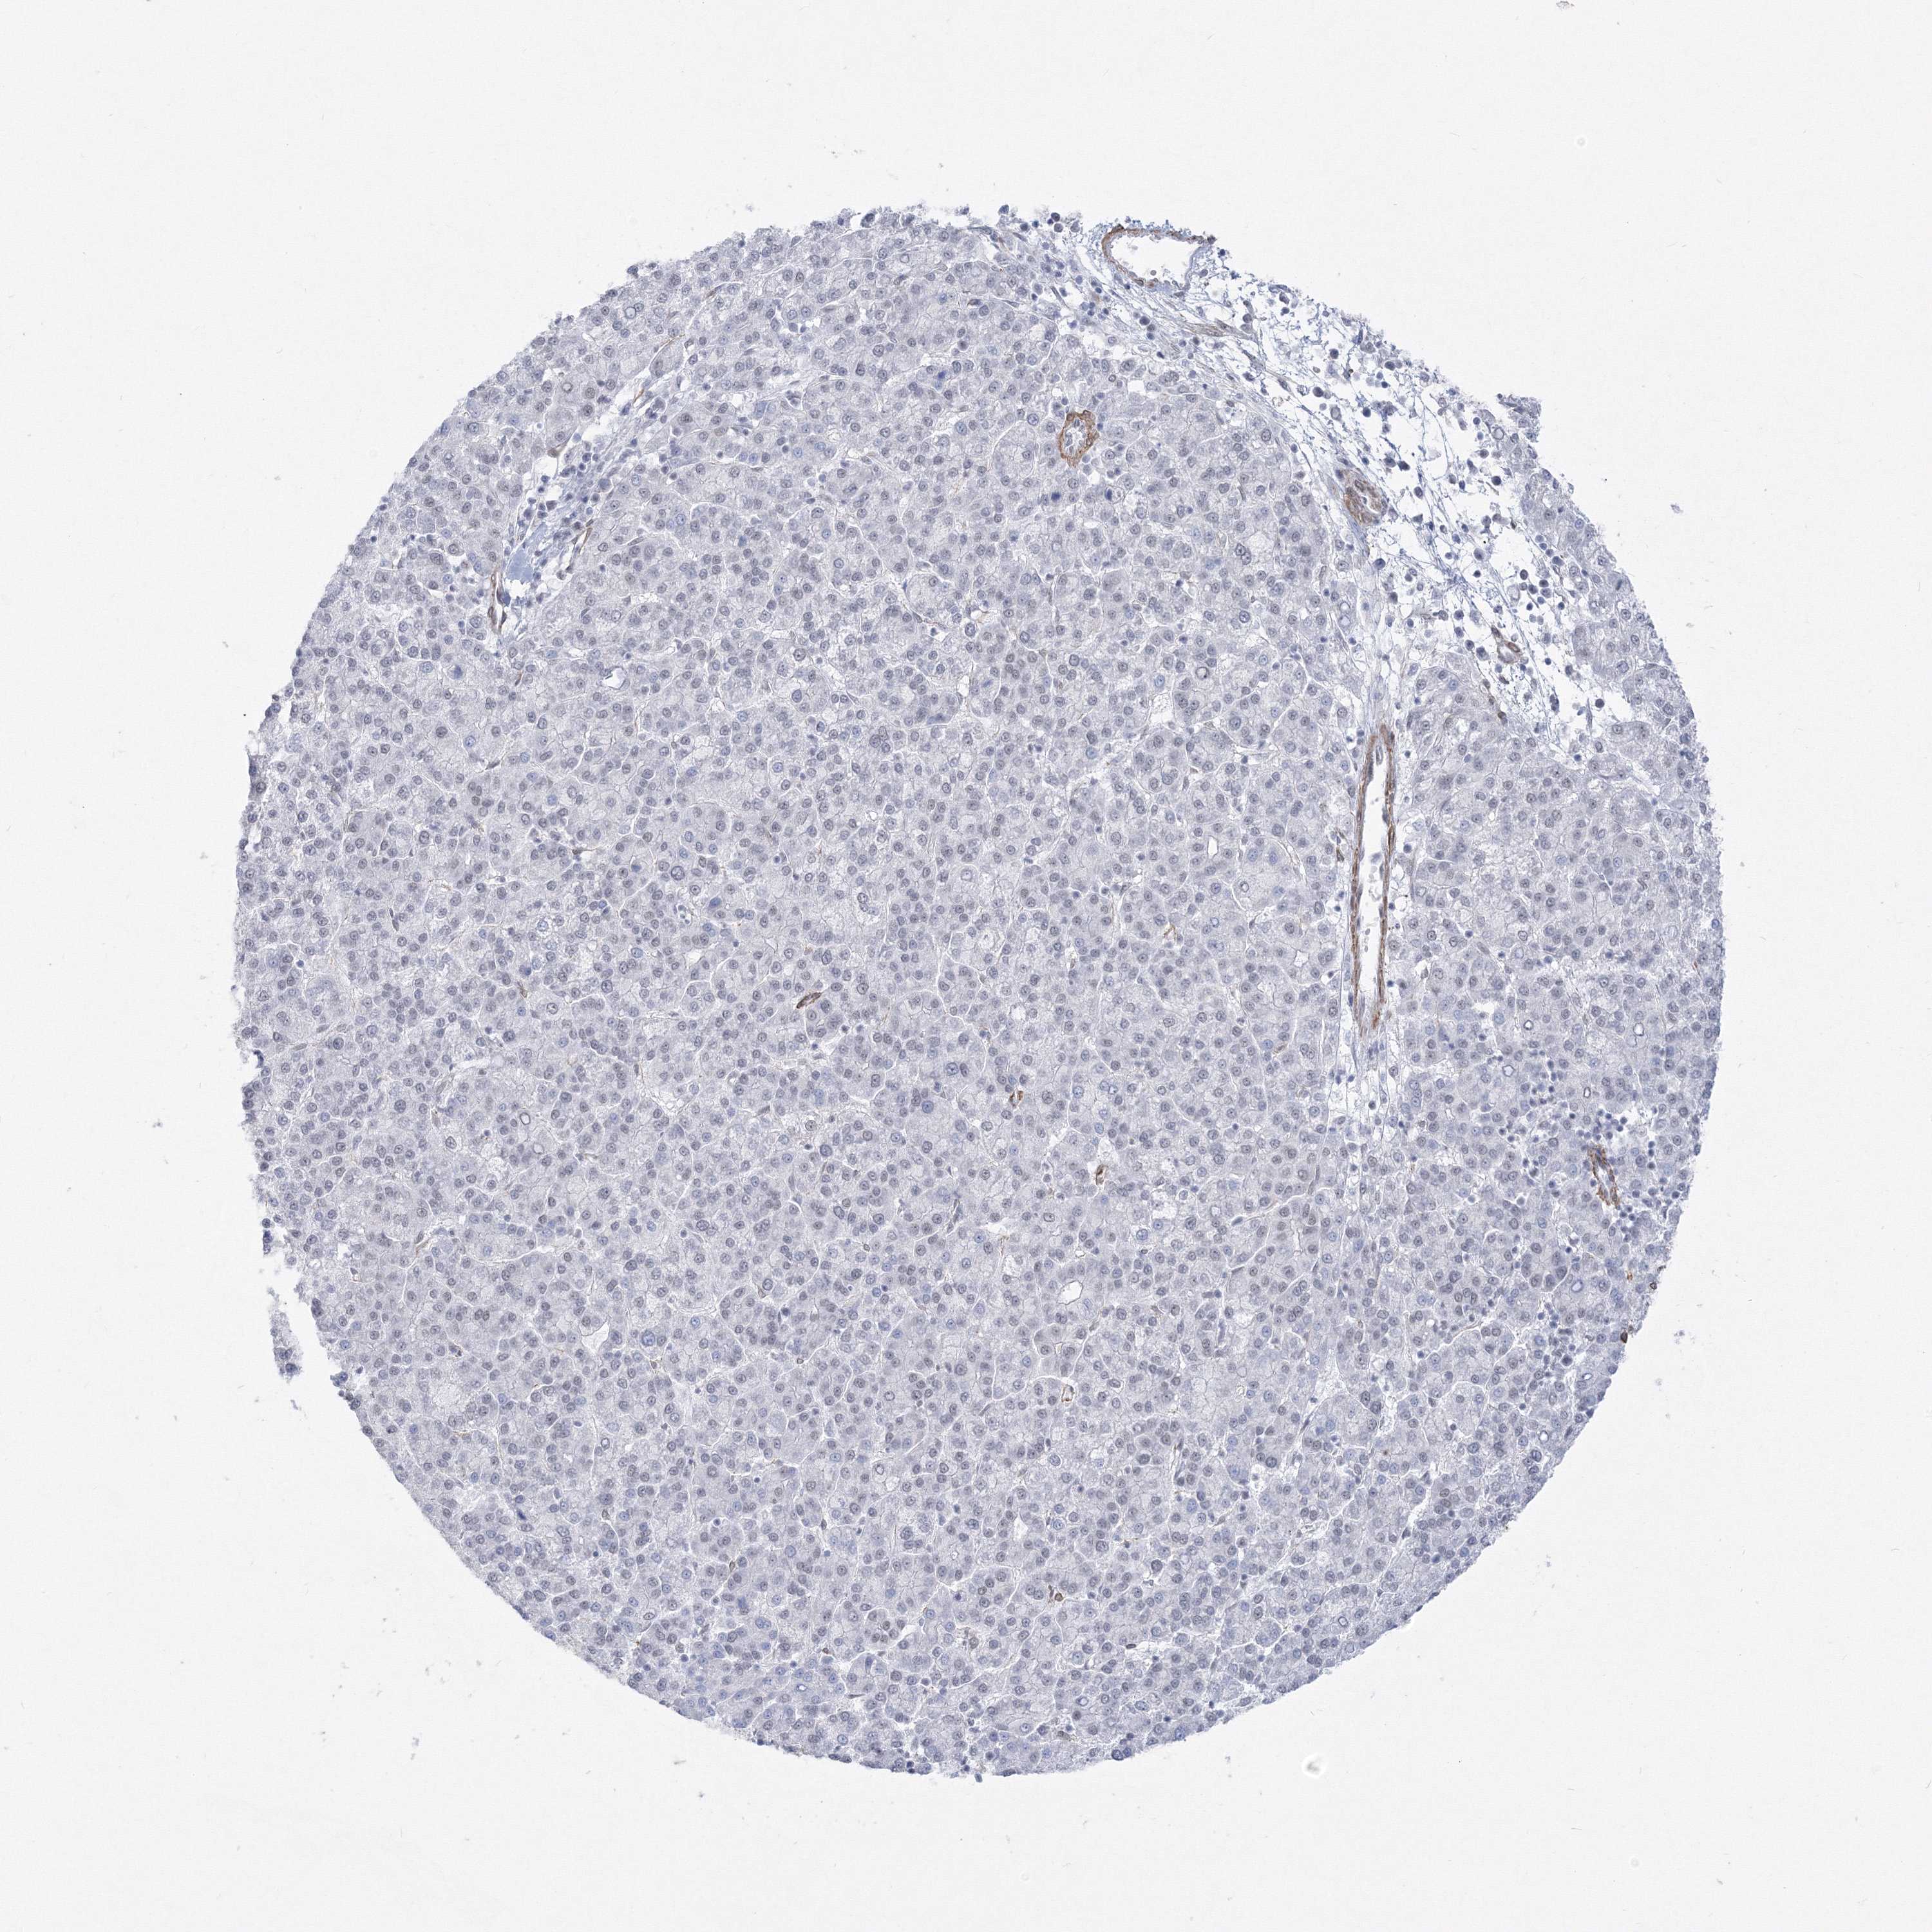

LIVER CANCER - Protein expressioni

A mouse-over function shows sample information and annotation data. Click on an image to view it in a full screen mode. Samples can be filtered based on level of antibody staining by selecting one or several of the following categories: high, medium, low and not detected. The assay and annotation is described here.

Note that samples used for immunohistochemistry by the Human Protein Atlas do not correspond to samples in the TCGA dataset.

Antibody stainingi

Antibody staining in the annotated cell types in the current human tissue is reported as not detected, low, medium, or high, based on conventional immunohistochemistry profiling in selected tissues. This score is based on the combination of the staining intensity and fraction of stained cells.

Each image is clickable and will lead to virtual microscopy that enables deeper exploration of all samples and also displays staining intensity scores, fraction scores and subcellular localization as well as patient and tissue information for each sample.

Antibody HPA036784

Staining

High

Medium

Low

Not detected

Intensity

Strong

Moderate

Weak

Negative

Quantity

>75%

75%-25%

<25%

None

Location

Nuclear

Cytoplasmic/membranous

Cytoplasmic/membranous,nuclear

Cholangiocarcinoma

Carcinoma, Hepatocellular, NOS